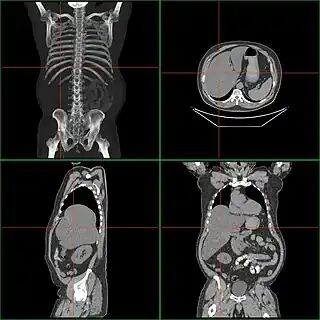

![]() Tomografía computarizada de un caso de hepatomegalia. | ||

La hepatomegalia es un aumento patológico del tamaño del hígado. Puede ser originada por diversas enfermedades.